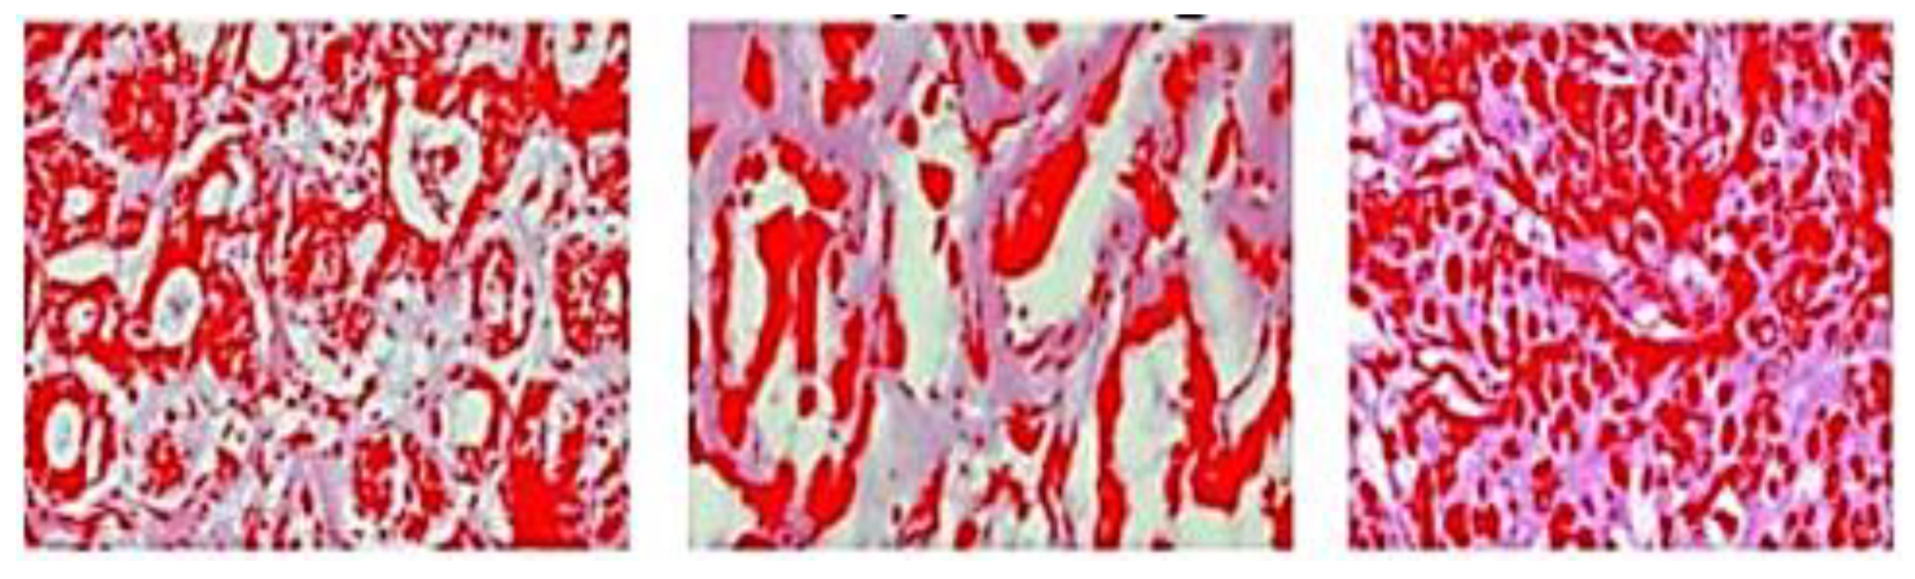

Y. Ouyang [105] developed a novel technique for classifying benign and malignant breast cancers based on H-scan ultrasound imaging to overcome common problem of ultrasound such as limited spatial resolution and speckle noise. In H-scan ultrasound images, benign breast tumors had more red components, whereas malignant breast tumors had more blue components, according to this researcher experimental findings as shown in Figure 15. The RGB channels of H-scan ultrasound images of benign and malignant breast tumors showed substantial variations. Y. Ouyang and team find that H-scan ultrasound imaging may be utilized to categorize benign and malignant breast cancers in a novel way.

Figure 15.

Ultrasound images of benign breast tumors and H-scan images [105].